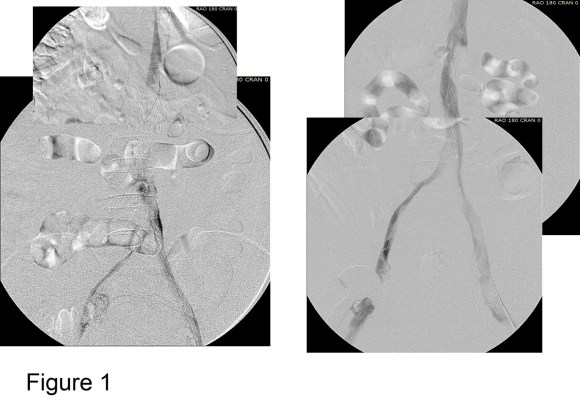

The figure below shows two panels with a Trapease filter associated with an iliocaval thrombosis. This patient had cardiovascular collapse and severe bilateral lower extremity edema after a long car ride.

Venography showed iliocaval thrombosis. Thrombolysis was started and the second panel on right of Figure 1 shows the result.

Large WallStents were used to support the recanalized iliocaval system from the common femoral veins to the filter. A Palmaz stent was deployed across the filter (Figure 2).